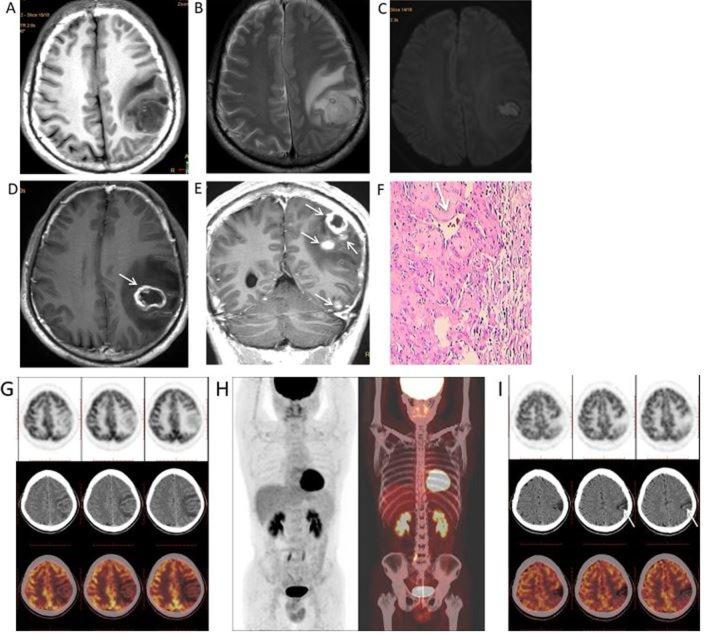

Cerebral syphilitic gumma is a rarely reported disease of the central nervous system. Magnetic resonance imaging (MRI) is an important diagnostic method for syphilitic gumma. The present study aimed to describe and characterize neuroimaging results from 6 patients with pathologically diagnosed cerebral syphilitic gumma. The 6 patients (age, 32-61 years) underwent brain CT and MRI, with 1 patient also undergoing whole-body 2-deoxy-2-(fluorine-18)fluoro-D-glucose-positron emission tomography/CT (18F-FDG PET/CT). Non-enhanced CT, conventional T1 weighted imaging (T1WI) and T2WI, diffusion weighted imaging (DWI) and gadolinium-enhanced T1WI images were acquired for all patients. The CT and MRI scans were retrospectively reviewed by two experienced radiologists for consensus on the location, number, size, T1WI, T2WI and DWI signal intensity characteristics, extent of vasogenic oedema, and enhancement patterns. In total, the 6 patients exhibited 10 lesions, nine of which were located in the cerebral hemisphere, primarily in the grey matter. The remaining lesion was located in the fourth ventricle, leading to mild-to-moderate hydrocephalus. The diameters of the identified 10 lesions ranged from 0.9-6.5 cm, with a mean diameter of 3.9 cm. The main feature observed in CT was low density and in MRI the features were T1WI and DWI hypointensity and T2WI hyperintensity. A single case exhibited syphilis gumma with massive haemorrhage. Ring-like or strip-like signs (n=5), accompanied by the dural tail sign (n=2) and homogeneous enhancement (n=1), were noted on T1WI with gadolinium. The 18F-FDG PET/CT performed in one patient of a cerebral syphilis gumma revealed low uptake and metabolism. The present study indicated that gadolinium-enhanced MRI combined with 18F-FDG PET/CT and laboratory examinations are helpful in distinguishing cerebral syphilitic gumma from brain tumors and infectious diseases, therefore avoiding unnecessary surgery.

脑梅毒瘤是一种中枢神经系统罕见病。磁共振成像(MRI)是诊断梅毒瘤的重要方法。本研究旨在描述和分析6例经病理诊断为脑梅毒瘤患者的神经影像学结果。这6例患者(年龄32 - 61岁)接受了脑部CT和MRI检查,其中1例还接受了全身2 - 脱氧 - 2 -(氟 - 18)氟 - D - 葡萄糖 - 正电子发射断层扫描/计算机断层扫描(18F - FDG PET/CT)。所有患者均采集了非增强CT、常规T1加权成像(T1WI)、T2WI、扩散加权成像(DWI)和钆增强T1WI图像。由两位经验丰富的放射科医生对CT和MRI扫描结果进行回顾性分析,就病变的位置、数量、大小、T1WI、T2WI和DWI信号强度特征、血管源性水肿范围及强化模式达成共识。6例患者共发现10个病灶,其中9个位于大脑半球,主要在灰质。其余1个病灶位于第四脑室,导致轻至中度脑积水。所发现的10个病灶直径范围为0.9 - 6.5 cm,平均直径为3.9 cm。CT主要表现为低密度,MRI表现为T1WI和DWI低信号、T2WI高信号。1例梅毒瘤伴有大量出血。钆增强T1WI可见5例呈环形或条状强化,2例伴有脑膜尾征,1例呈均匀强化。1例脑梅毒瘤患者的18F - FDG PET/CT显示摄取和代谢减低。本研究表明,钆增强MRI联合18F - FDG PET/CT及实验室检查有助于脑梅毒瘤与脑肿瘤和感染性疾病的鉴别,从而避免不必要的手术。